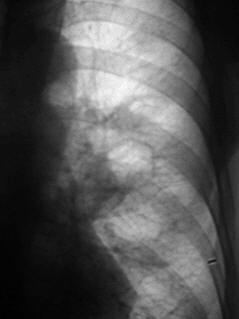

Перисциссурит слева.